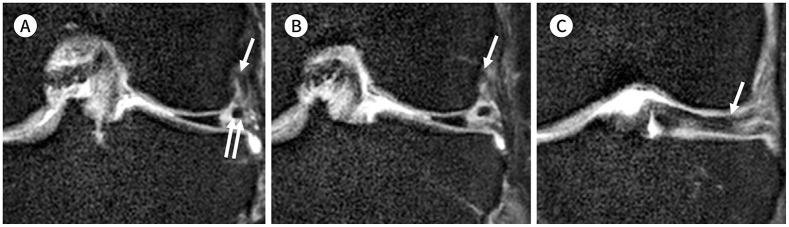

To accurately interpret knee MRI, it is important not only to know the basic meniscal anatomy but also to distinguish it from that under pathological conditions. Thus, it would be helpful to know the normal meniscus variants (false positives) that could be mistaken for meniscal tears, and tears that could easily be missed and incorrectly diagnosed as normal (false negatives). False positives include synovial recesses, meniscal flounce, the relationship between the popliteus tendon and lateral meniscus, transverse ligament, the anterior root of the meniscus, and meniscofemoral ligament. False negatives include focal radial tears, flap tears, posterior root tears, meniscocapsular separation, and discoid meniscal tears. In this pictorial essay, we reviewed the imaging data obtained in the aforementioned cases.

为了准确解读膝关节磁共振成像(MRI),不仅要了解半月板的基本解剖结构,还要将其与病理状态下的情况区分开来。因此,了解可能被误诊为半月板撕裂的正常半月板变异(假阳性)以及容易被漏诊并错误诊断为正常情况(假阴性)的撕裂情况会有所帮助。假阳性包括滑膜隐窝、半月板皱襞、腘肌腱与外侧半月板的关系、横韧带、半月板前根和半月板股骨韧带。假阴性包括局灶性放射状撕裂、瓣状撕裂、后根撕裂、半月板关节囊分离和盘状半月板撕裂。在这篇图文文章中,我们回顾了上述病例中获得的影像数据。